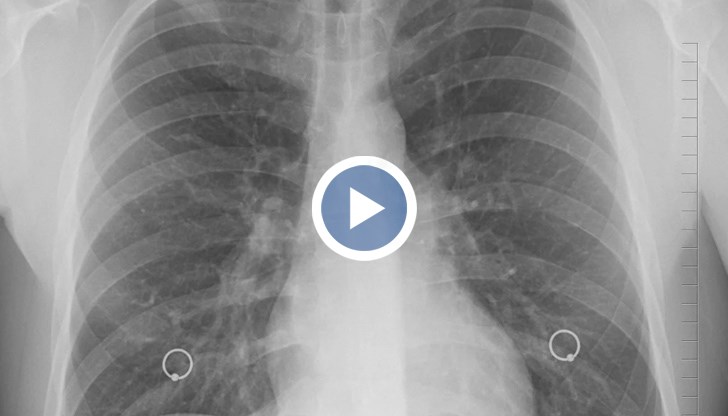

Антигенните тестове ще бъдат приравнявани с PCR и също ще се отчитат в регистрите. Това обяви здравният министър Костадин Ангелов. Той каза още, че са осигурени 1 200 000 антигенни теста

Признаването на антигенните тестове ще помогне за по-точна статистика на носителите на заразата, като така и повече хора с коронавирус ще подлежат на карантина. Въпреки че PCR тестовете са по-точният начин за доказване на наличие на вируса, все повече антигенни тестове се оказват достоверни над 90%. Знаете, бързите тестовете дават резултат за минути, позволяват да се изследват много повече хора и по-бързо да се събере информация за епидемиологичната обстановка у нас. Бързите антигенни тестове ще бъдат и по-изгодни финансово за хората. Очаква се антигенните тестове да бъдат приравнени на PCR тестовете след 21 декември. Всички близо 1 200 000 антигенни теста ще стигнат до края на тази седмица до всички РЗИ-та, а от там и до лечебните заведения. Днес стана ясно и, че лични предпазни средства има достатъчно за всички. Колкото до мерките - рано е да се говори за разхлабването им след 21 декември, а тази седмица ще бъде решаваща.

Хората с наличие на клинична картина и позитивен антигенен тест вече също ще влизат в статистиката.

Проф. Костадин Ангелов, министър на здравеопазването: Пациентите, които имат положителен антигенен тест и клинична картина ще попадат в хипотезата на позитивен пациент с доказан COVID-19. Съответно той трябва да бъде в изолация 14 дни и съответно неговите контактни от първи ред да бъдат в карантина, която е 10-дневна, както е с PCR тестовете.